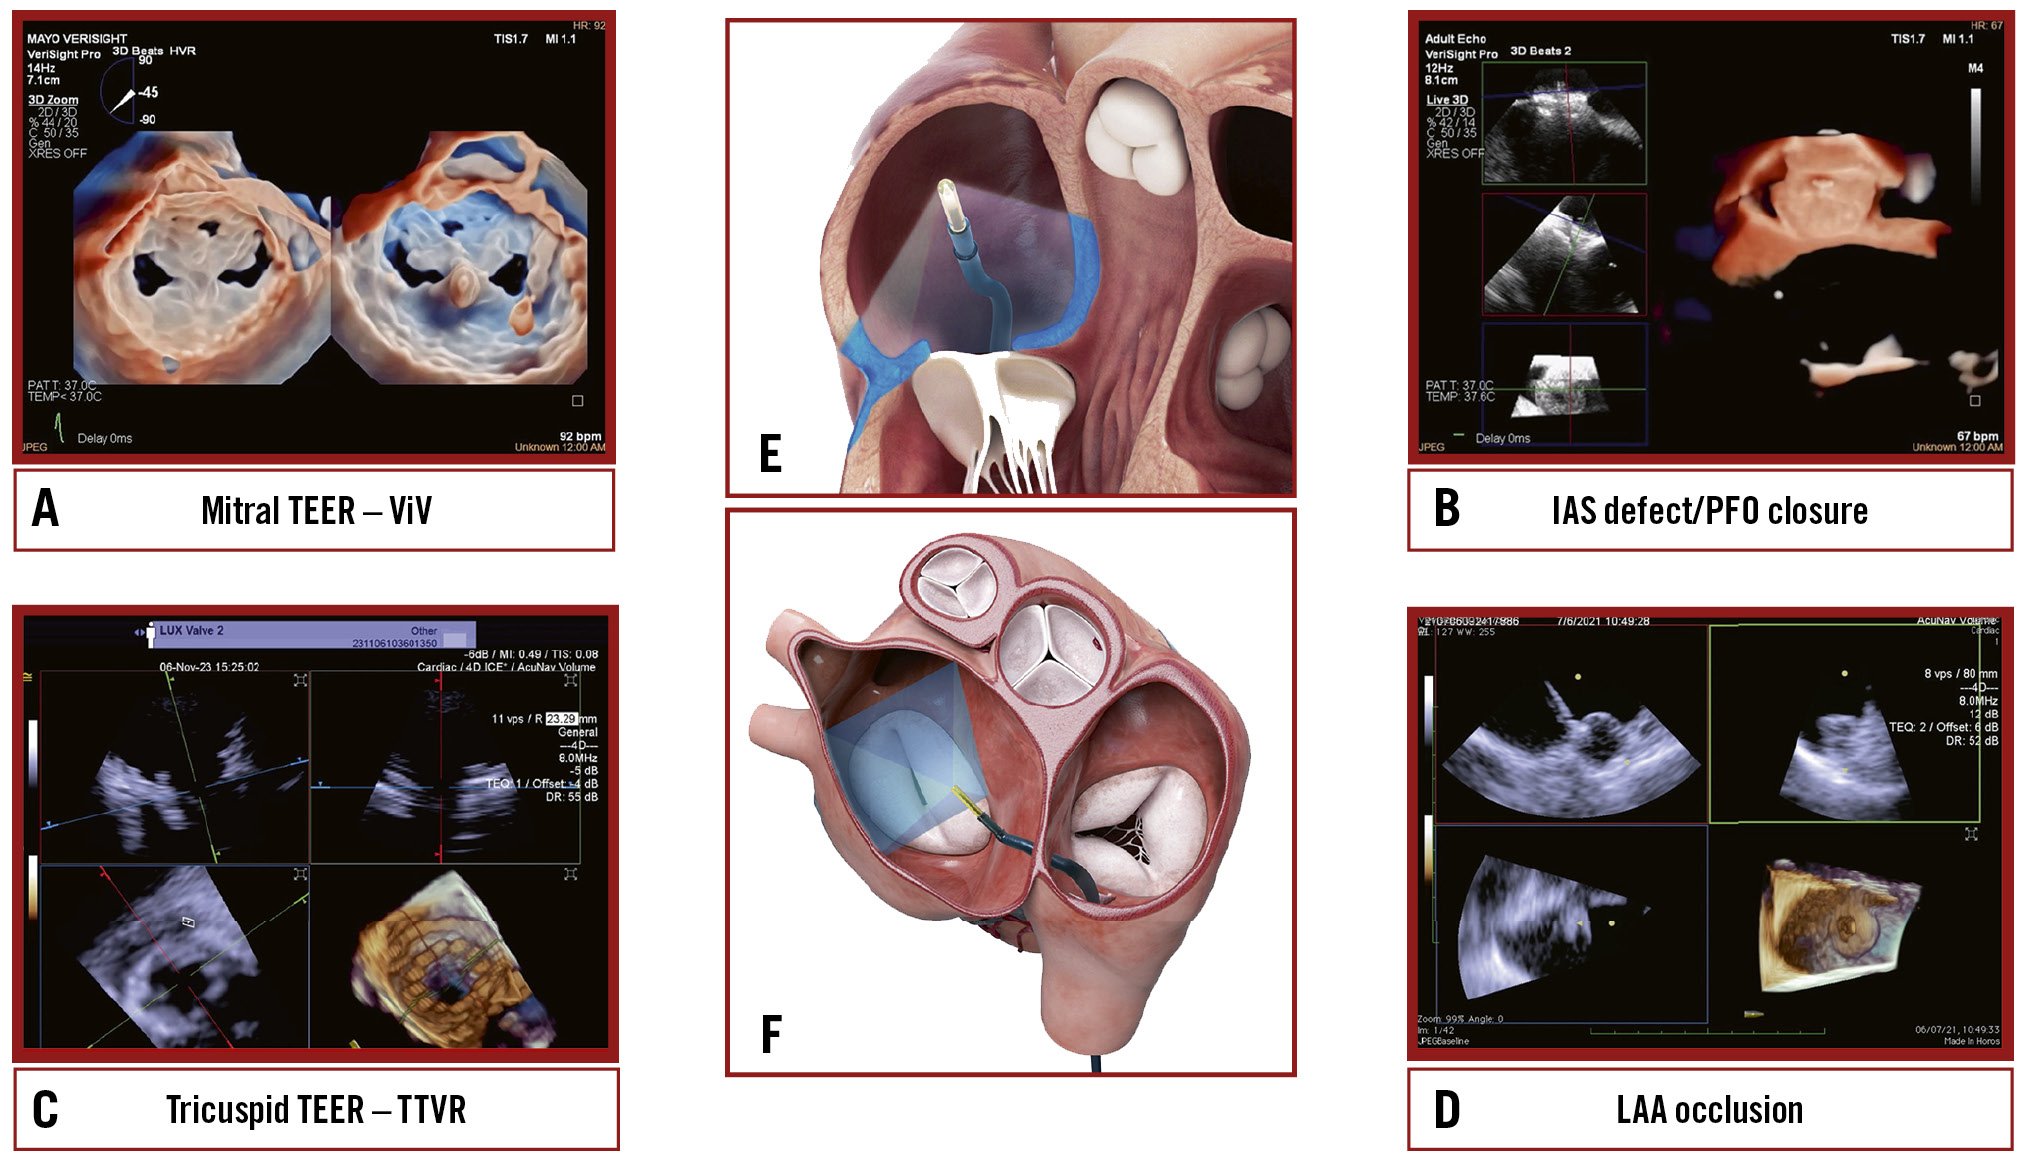

Central illustration. Current landscapes on 3D ICE utilisation. An overview of the key structural heart interventions that increasingly utilise 3D ICE: (A) mitral TEER/ViV; (B) IAS defect/ PFO closure; (C) Tricuspid TEER/TTVR; (D) LAAO. E) An illustration of the ICE probe’s position during imaging of the tricuspid valve. F) An illustration of the ICE probe’s position during imaging of the mitral valve. 3D: three-dimensional; ICE: intracardiac echocardiography; IAS: interatrial septum; LAAO: left atrial appendage occlusion; TEER: transcatheter edge-to-edge repair; TTVR: transcatheter tricuspid valve replacement; ViV: valve-in-valve